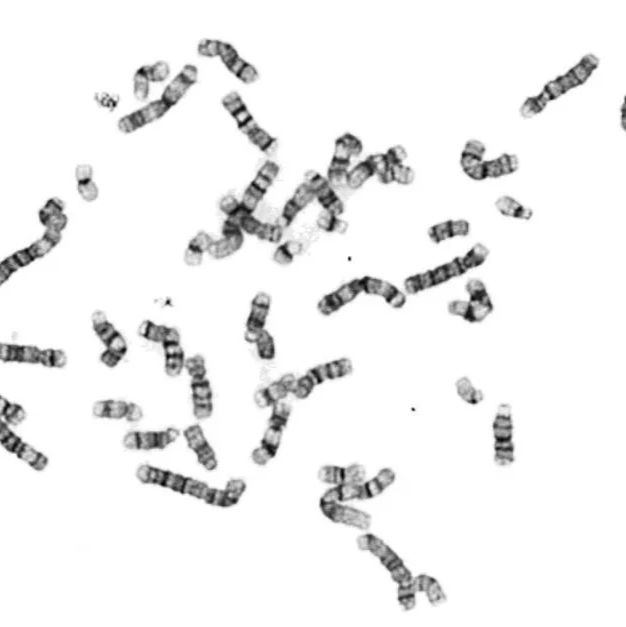

细胞染色体核型分析